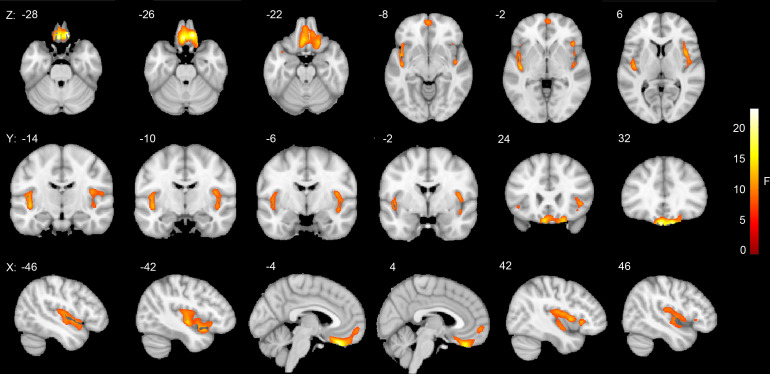

Results: Whole-brain voxel-wise analysis revealed significant changes of OEF primarily in the limbic system, including the orbitofrontal cortex and bilateral insular lobes, among HC, non-NPSLE and NPSLE groups. Regional analysis indicated reduced OEF values in subregions of the amygdala, hippocampus and caudate nucleus in non-NPSLE compared with HC, with decreasing trends observed in all selected regions of subcortical grey matter structures. In the right hippocampus, OEF values were increased in NPSLE patients compared with non-NPSLE patients. Considering all subjects in the study, OEF values in the bilateral medial amygdalae, right lateral amygdala, left rostral hippocampus and right dorsal caudate nucleus were positively correlated with MoCA scores.